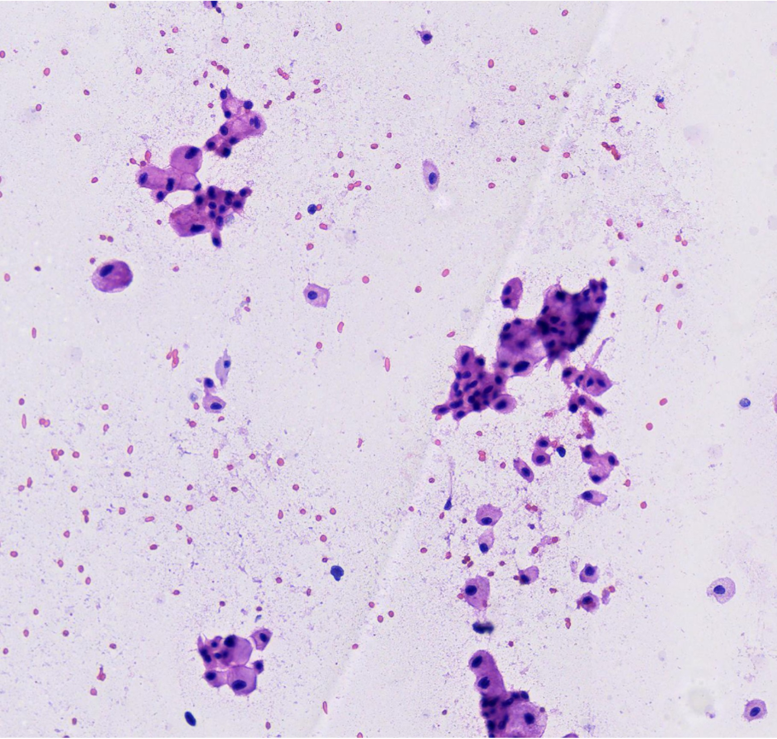

Paciente mujer de 43 años, G0-P000 con antecedentes de hipertensión arterial en tratamiento e historia familiar de cáncer (carcinoma de células de Merkel). Acude por presentar dolor punzante en flanco izquierdo de una semana de evolución. Al examen físico, se palpa masa abdominal móvil y dolorosa. La TC abdominal revela masa sólida ovoidea, de bordes definidos y aspecto encapsulado que mide 139 x 105 mm, asociada a áreas quísticas (Fig 1). Ante estos hallazgos, se realiza nefrectomía radical izquierda. Con la intención de tomar decisiones clínicas inmediatas, se realiza impronta del tumor renal en pieza operatoria observándose células tumorales poligonales con abundante citoplasma eosinofílico granular, membrana citoplasmática bien definida y bordes celulares acentuados. El resultado fue neoplasia de tipo oncocítica que favorece carcinoma cromófobo (Fig 2-5), confirmado histológicamente (Fig 6). Paciente evoluciona favorablemente.

El carcinoma cromófobo de células renales presenta rasgos citológicos característicos, como células poligonales con citoplasma abundante eosinofílico o reticular y membranas celulares bien definidas. Sin embargo, hallazgos clásicos como los halos perinucleares y núcleos arrugados pueden no ser tan evidentes, como en nuestro caso, generando solapamiento con el oncocitoma, principal diagnostico diferencial, que muestra mayor monotonía celular y citoplasma homogéneo, sin reticulación ni vacuolización.3

En la impronta citológica, los bordes bien delimitados permitieron orientar nuestro diagnóstico hacia un carcinoma cromófobo. Esta técnica constituye una herramienta diagnóstica útil en el intraoperatorio para toma de decisiones rápidas contribuyendo así a una adecuada planificación quirúrgica y manejo terapéutico del paciente.